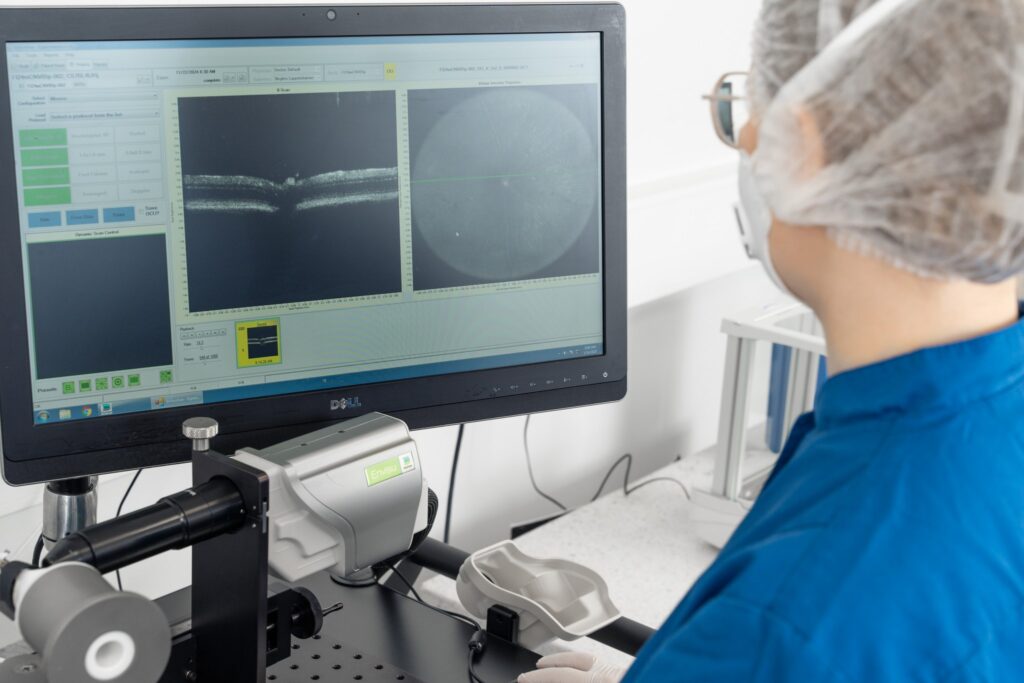

– Quantitative evaluation of inner retinal layer thickness using SD-OCT and AI-driven algorithms

Non-invasive monitoring of pathology

Application of 3Rs using in vivo imaging, functional assessment and behavioral analysis.